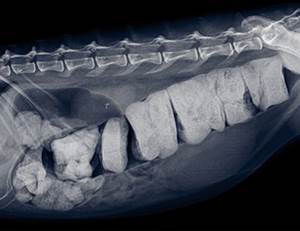

Ущемление и расширение толстой кишки встречается во всех случаях мегаколона. Может потребоваться рентген, так как бывает трудно дифференцировать эту патологию от неоплазии. У кошек с вегетативной дистонией будут признаки других нарушений, таких как недержание мочи, регургитация, мидриаз, выпадение третьего века и брадикардиия. Ректальное обследование под седацией или анестезией должно быть выполнено у всех кошек, чтобы исключить перелом таза и его неправильное сращение, дивертикул прямой кишки, перинеальную грыжу, аноректальную стриктуру, инородное тело, неоплазию или полипы. Неврологическое обследование также необходимо, чтобы обнаружить любые неврологические причины запора, включая травму тазового нерва, повреждение спинного мозга или деформации спинного мозга Мэнкских кошек.

Необходимо выполнить рентгенографию брюшной полости. Рентгенограммы помогут выявить предрасполагающие факторы, такие как перелом таза, внепросветное образование, инородное тело и патологии спинного мозга. Ущемление отделов толстого кишечника, само по себе, не подразумевает необратимого мегаколона.